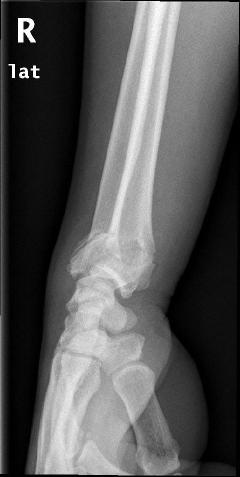

Περίπτωση 1ου ασθενούς